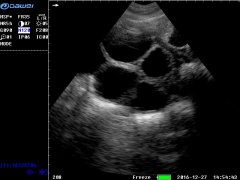

高危胎兒診治技術_雙胎妊娠超聲檢查技術規(guī)范

雙胎超聲檢查量亦呈上升趨勢, 據該項目組中具有代表性的中國醫(yī)科大學附屬盛京醫(yī)院統計: 2016年雙胎超聲檢查人次數(5235人次)是2013年 (1917人次)...